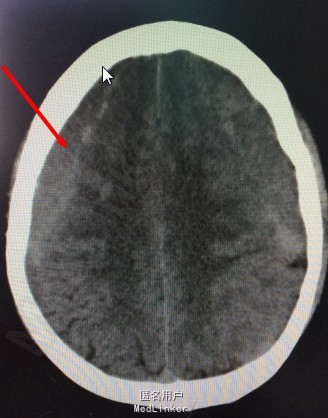

患者,男;62岁,主诉:反复阵发性头痛2个月。现病史:患者2个月劳累后突发性头痛,疼痛首先位于双侧枕部,逐渐累及双侧额、颞部,每次疼痛约30分钟,平卧后可稍缓解,伴恶心,呕吐,为喷射性,呕吐物为胃容物;无昏迷,肢体活动可,无大小便失禁,曾就诊于当地医院,给予保守治疗约20天,症状未见明显缓解;1周前患者来我院就诊,行头颅MRI示,双侧额、颞、顶、枕硬膜下血肿,可疑右顶血管畸形。现为求进一步诊治而入我院。

初步诊断:慢性硬膜下血肿 处理:慢性硬膜下血肿钻孔引流术

慢性硬膜下血肿是指颅内出血血液积聚于硬脑膜下腔、伤后三周以上出现症状者。目前对于血肿的出血来源和发病机理尚无统一的认识。其发生率约占颅内血肿的10%,血肿常发生于额顶颞半球凸面,积血量可达100-300毫升。临术表现以颅内压增高为主,头痛较为突出,部分有痴呆、淡漠和智力迟钝等精神症状,少数可有偏瘫、失语和局源性癫痫等局源性脑症状。 首选的方法是钻孔引流,疗效堪称满意,如无其他并发症,预后多较良好。